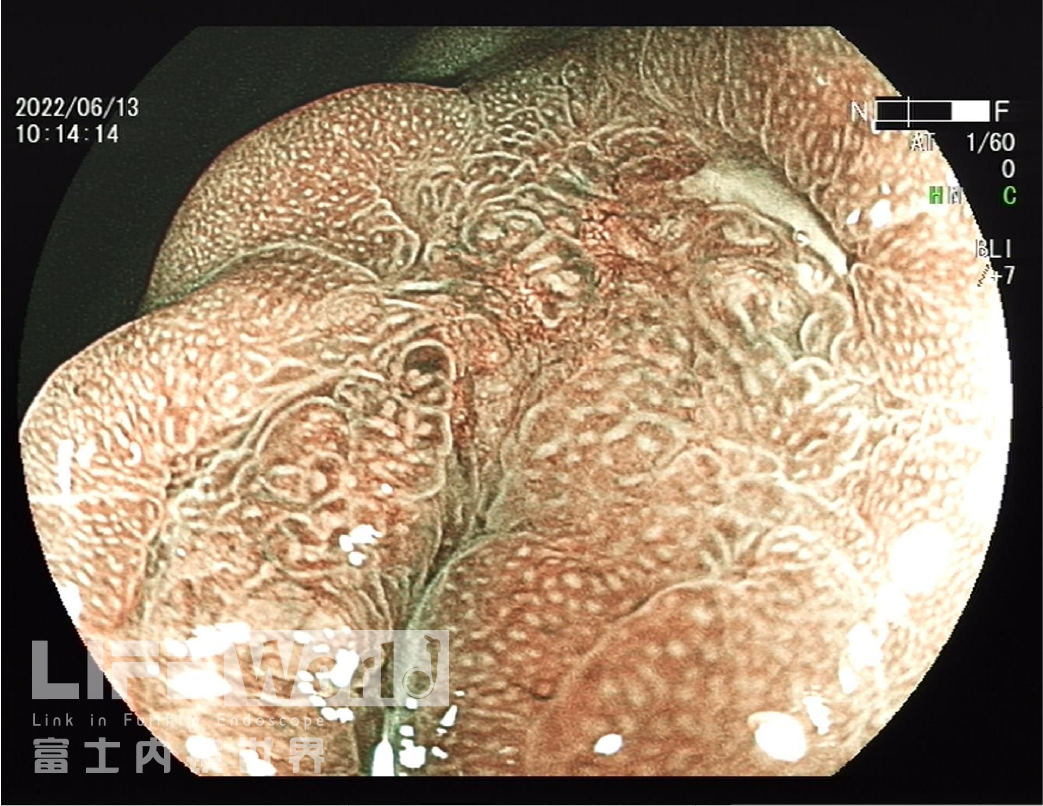

BLI模式低倍放大观察,可清晰的勾勒出病变的范围,病变的口侧端表面微结构的异型性明显,考虑为癌灶,病变的肛侧端异型性不明显,考虑为上皮内瘤变。

对考虑为癌灶的区域进行中倍放大观察:IMSP(+), IMVP(+)。

对考虑为癌灶的区域进行高倍放大观察,根据下面的胃癌放大内镜诊断流程图来进行判断。